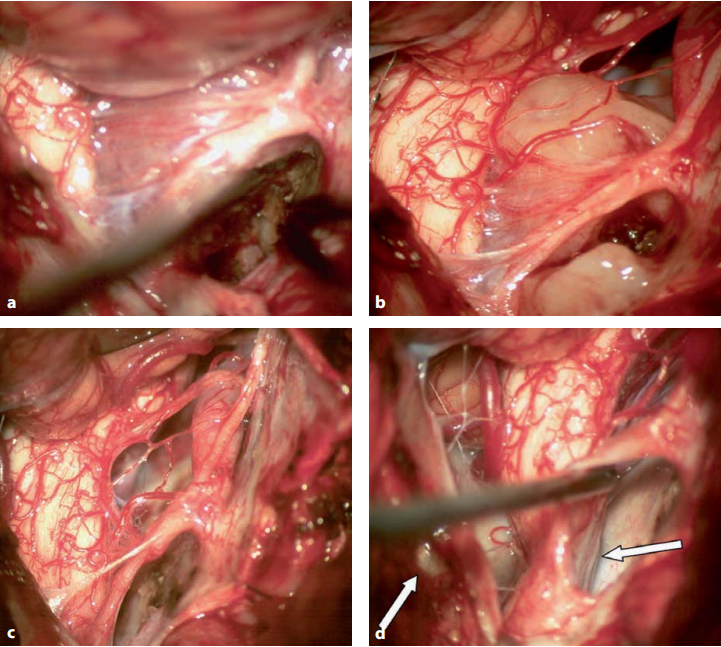

典型的腦膜瘤常伴有硬腦膜浸潤(rùn),這是其血管供應(yīng)的部位(圖13.13)。一些腦膜瘤表現(xiàn)為“斑塊狀”生長(zhǎng);另一些腦膜瘤的硬腦膜附著區(qū)有限且小于腫瘤直徑。在臨床中,這是兩種不同的情況。當(dāng)“斑塊狀生長(zhǎng)”的腦膜瘤有較高的出血傾向和需要更多的術(shù)中電凝凝固時(shí),切除小面積腦膜瘤很容易進(jìn)行。此外,后一種腫瘤也傾向于包繞顱神經(jīng)IX-XII,并侵犯舌下神經(jīng)管和頸靜脈孔的神經(jīng)部分,使切除更加困難。在這兩種情況下,基本原則是切開一齒狀韌帶,電凝凝固阻斷腦膜瘤的血供(圖13.13)。下一步,將較靠近腹側(cè)硬腦膜的腫瘤部分切除,以創(chuàng)造一個(gè)手術(shù)術(shù)野,使剩余的背側(cè)腫瘤部分沿著從下腦干向硬膜腹側(cè)的方向逐步移動(dòng)(圖13.14)。在這個(gè)動(dòng)作中,應(yīng)盡努力避免壓迫周邊神經(jīng)。寰樞椎背弓(dorsal atlantal arch)的水平通常是神經(jīng)較大受壓的部位(圖13.14)。在這種情況下,與C1半椎板切除術(shù)相比,在打開硬腦膜之前進(jìn)行C1椎板磨除是有幫助的,以避免在硬膜內(nèi)操作時(shí)對(duì)神經(jīng)造成任何額外的牽拉壓迫。

圖13.13 a,b術(shù)前MR圖像(T1-W增強(qiáng)掃描,b矢狀T2-W)顯示一個(gè)大的枕大孔腦膜瘤,該腦膜瘤向背側(cè)生長(zhǎng),嚴(yán)重壓迫頸髓。c、圖示硬腦膜切開,腫瘤的背外側(cè)和腹側(cè)部分暴露,通過(guò)側(cè)面反射硬腦膜和椎動(dòng)脈的遠(yuǎn)端V3部分。e、f相應(yīng)的術(shù)中照片顯示通過(guò)側(cè)面反射硬腦膜,可以直接接觸到腫瘤基底的硬腦膜(VA,椎動(dòng)脈)

圖13.14腫瘤的術(shù)中照片如圖13.13所示。a:首先,分離腫瘤和周邊血管及腦組織,阻斷腫瘤血供。這種斷流術(shù)是在對(duì)側(cè)顱尾側(cè)進(jìn)行,直到整個(gè)腫瘤與血管供應(yīng)分離。b:剩下的無(wú)血管腫瘤部分現(xiàn)在可以從顱神經(jīng)的根上輕輕地分開,并分塊切除腫瘤。c:腫瘤完全切除后,見(jiàn)顱神經(jīng)扭曲,椎動(dòng)脈近端V4部分和顱神經(jīng)未見(jiàn)腫瘤。d:C1水平是上頸髓受壓較大的部位,腫瘤壓迫神經(jīng)壓迫寰樞椎弓。